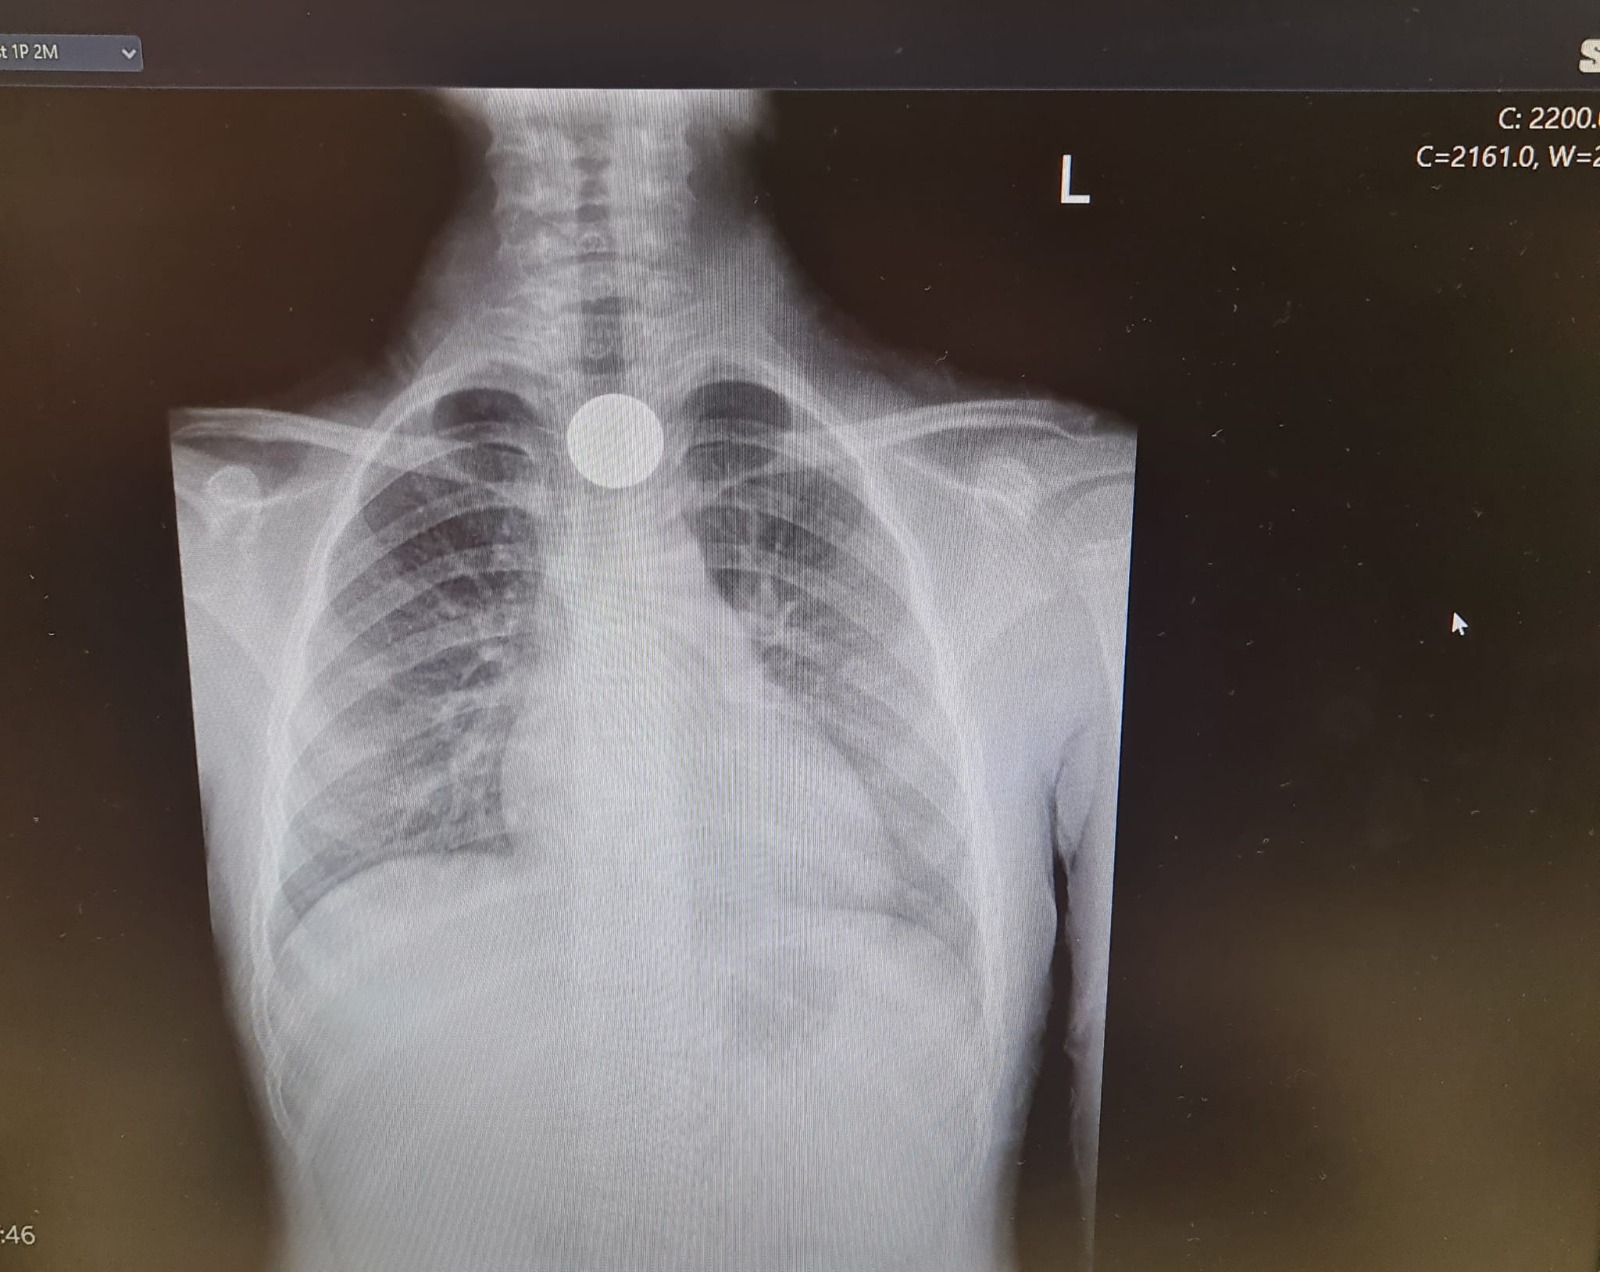

כהן הללי, ילדה בת 6 וחצי מאשקלון, בלעה אתמול מטבע של 10 אגורות בבית הספר. הללי הגיעה למיון, נשלחה לצילום, שבו נצפה מטבע בוושט. המטבע הוצא בפעולת גסטרוסקופיה. הללי התאוששה ושוחררה לביתה במצב טוב.

מצ"ב תמונת שיקוף של המטבע ותמונה של הללי עם אמה.